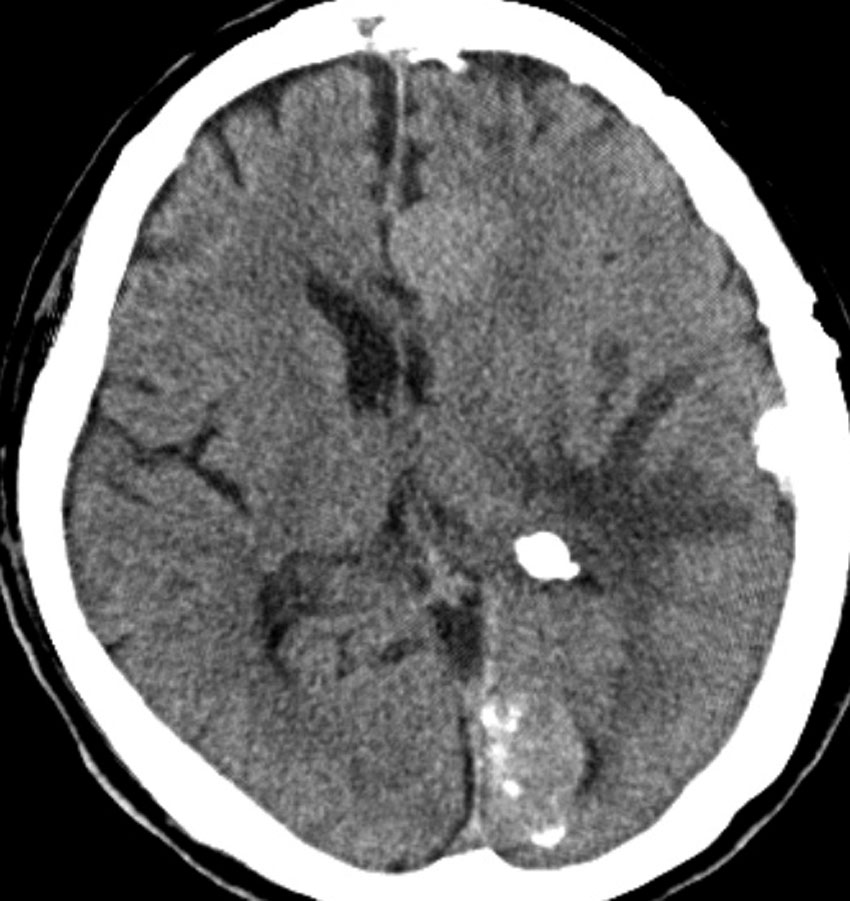

全髄膜の腫瘍化,NF-2

テント下を含めて頭蓋内の全ての髄膜が同時に腫瘍化してきます。この患者さんはNF-2なのですが,NF-2がない患者さんにもmeningiomatosisはあります。脳圧亢進による視神経乳頭萎縮で両側の視力が無くなるというような症状が出ます。これは手術適応がないタイプです。